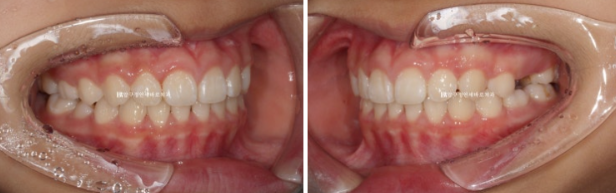

24.09

재제작 총 2번 했고 토탈치료기간은 2년 중간에 쉬는 시간은 5개월 이었습니다.

22.08~24.09

돌출된 앞니 개선

처음에는 어린이였으나 2년 사이 어엿한 청소년이 되었습니다.

앞니 각도 스마일라인 모두 좋습니다.

앞니 돌출이 개선이 되면 입이 비로소 편하게 다물어집니다.

이정도 결과가 나오면 성인이 되어서도 굳이 교정을 안해도 됩니다.